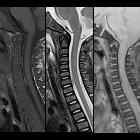

MRI

MRI is the imaging modality of choice for identifying and characterizing subdural hematomas.

Signal characteristics will vary, depending on the age of the blood.

After having confirmed the location of the collection as subdural on axial images, sagittal images can be utilized for measuring its extent.